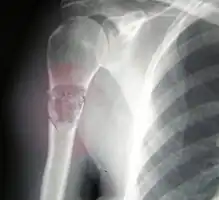

Osteosarcomas tend to occur at the sites of bone growth, presumably because proliferation makes osteoblastic cells in this region prone to acquire mutations that could lead to transformation of cells (the RB gene and p53 gene are commonly involved). Due to this tendency, high incidence of osteosarcoma is seen in some large dog breeds (St. Bernards and Great Danes). The tumor may be localized at the end of the long bone (commonly in the metaphysis). Most often it affects the proximal end of tibia or humerus, or distal end of femur. Osteosarcoma tends to affect regions around the knee in 60% of cases, 15% around the hip, 10% at the shoulder, and 8% in the jaw. The tumor is solid, hard, irregular ("fir-tree," "moth-eaten", or "sun-burst" appearance on X-ray examination) due to the tumor spicules of calcified bone radiating in right angles. These right angles form what is known as a Codman triangle, which is characteristic but not diagnostic of osteosarcoma. Surrounding tissues are infiltrated.

Family physicians and orthopedists rarely see a malignant bone tumor (most bone tumors are benign). The route to osteosarcoma diagnosis usually begins with an X-ray, continues with a combination of scans (CT scan, PET scan, bone scan, MRI) and ends with a surgical biopsy. A characteristic often seen in an X-ray is Codman's triangle, which is basically a subperiosteal lesion formed when the periosteum is raised due to the tumor. Films are suggestive, but bone biopsy is the only definitive method to determine whether a tumor is malignant or benign.